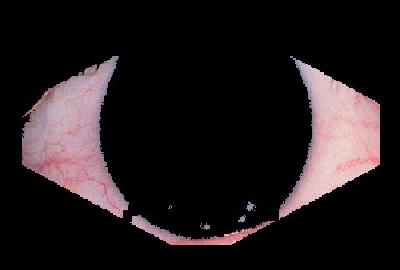

The feature that was examined in the first part of this workshop was that of conjunctival hyperaemia. Conjunctival hyperaemia refers to the presence and abundance of blood vessels in the conjunctiva, the layer of tissue covering the sclera. As an eye becomes increasingly more irritated, the presence and size of blood vessels in the conjunctiva increases correspondingly, resulting in a red appearance. This redness is caused by the eye's immune response to an irritant, either a foreign object or the presence of an irritating solution. For example, while the eye in Figure 2 has very little irritation, the eye shown in Figure 3 shows severe conjunctival hyperaemia.

| Figure 2: A healthy eye | Figure 3: An unhealthy eye | |

Our defined area of concern for the grading of the images is the sclera on both sides of the iris and pupil. This area was chosen because it has been shown that practitioners base their rating of conjunctival hyperaemia (ocular redness) on overall coverage by vessels rather that the appearance of individual vessels [7].

The current method for isolating the shape used for redness evaluation is to use simple colour thresholding to locate the iris, and geometry to remove the eyelids and fold. An example of the desired output is shown below in Figure 6. This shape was chosen because is it the closest approximation to what would be seen by a human observer grading the eye. In theory it will minimize the amount of information lost.